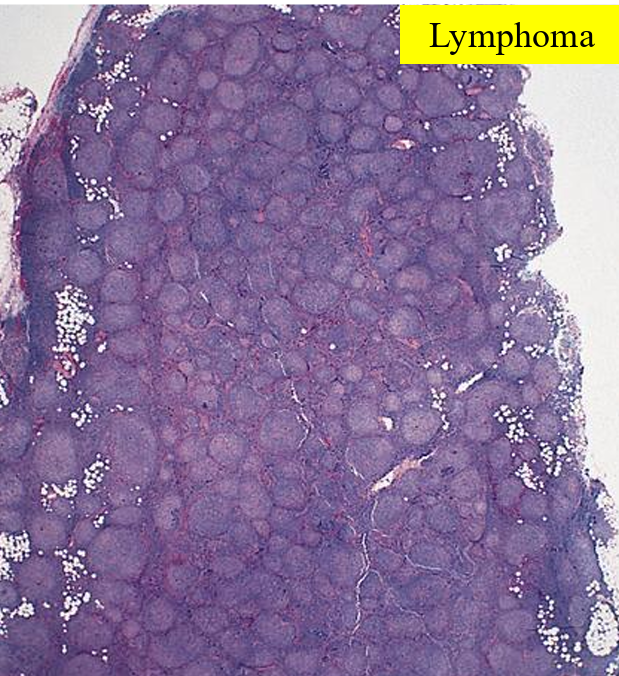

Follicular lymphoma

(defintion + pathogenesis + diagnosis + treatment + prognosis)

Low grade B-cell NHL causing B-cell lymphocytes to be arranged in follicular pattern in LN’s. Commonly affects >50yrs

Pathogenesis: translocation of BCL2 gene on chr 18 with IgH gene on ch 14, causing overexpression on BCL2 gene which inhibits apoptosis. This forms a clone of mature B cells which fail to die by apoptosis, resulting in geriatric overcrowding

Diagnosis:

Signs non-contiguous lymphadenopathy, fever, night sweats, weight loss

CD19 & CD20 positive immunohistochemistry

Treatment: Chemotherapy and/ or immunotherapy (e.g.rituximab)

Prognosis: not curable, survival 7-9 years